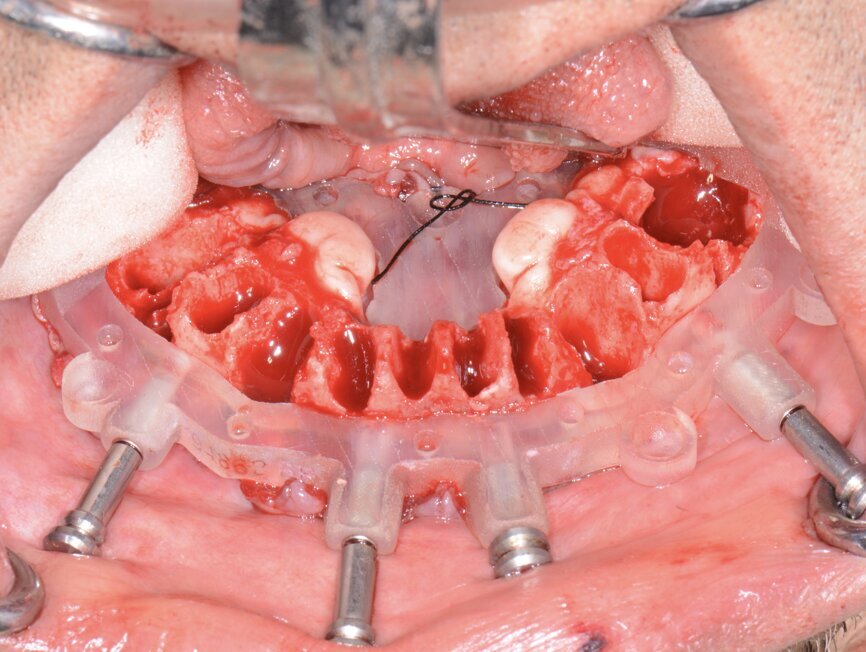

Once the appropriate bone levelling had been accomplished with the surgical handpiece, the universal implant surgical guide was positioned into the bone levelling guide and the sites for the implants were initiated with a designated 1.8 mm pilot drill in its appropriate key from the OCO Biomedical Guided Surgical System Kit (Fig. 11), utilising the Mont Blanc surgical handpiece (Anthogyr) and AEU 7000 surgical motor (Aseptico) at a speed of 1,200 rpm with copious amounts of sterile saline. Sequential osteotomy formers and keys from the OCO Biomedical Guided Kit were then used to shape the final osteotomies. Once the osteotomies were complete, a rotary implant driver was used to place the dental implants until increased torque was necessary (Fig. 12). The ratchet wrench was then connected to the adapter and the implants torqued to final depths, reaching a torque level of about 40–50 Ncm.

A baseline Implant Stability Quotient reading was taken of these implants utilising the Penguin RFA unit (Aseptico). Since the initial readings were all above 70 and the quality of bone after levelling was good, multi-unit abutments (OCO Biomedical) were tightened into the Engage dental implants at 25 Ncm, followed by temporary cylinders at 15 Ncm. Any residual areas around the implants or in the sockets were grafted with a cortical mineralised and demineralised bone grafting material to optimise the area for regeneration (Fig. 13).